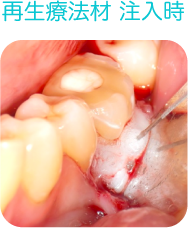

歯周ポケットの除去、環境改善、再生療法

歯周組織の再生